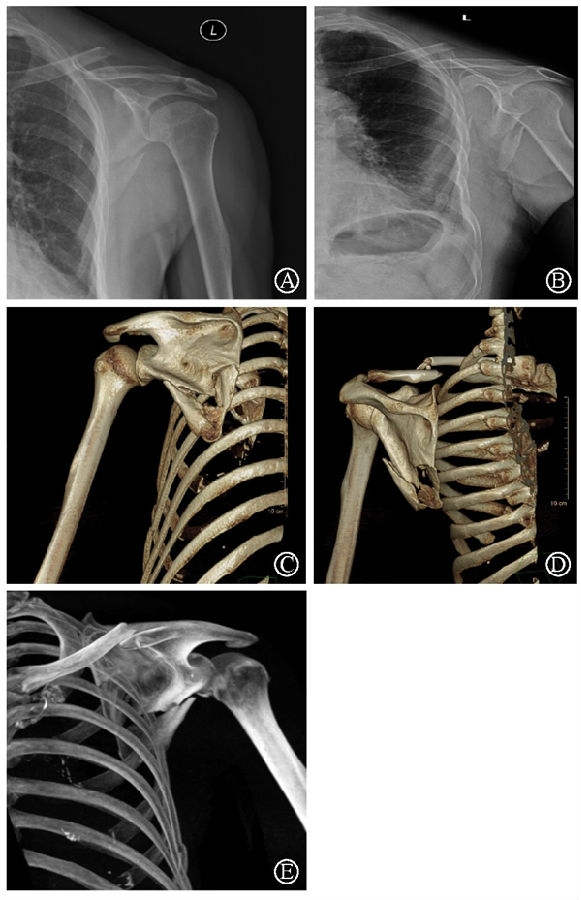

病例2为1例累及肩胛盂、肩胛颈和肩胛骨体部的复杂肩胛骨骨折(图11-12)。

术前设计采用跨骨折区域钢板螺钉固定(图13)。术中可见纵向骨折区域骨质薄弱,骨折粉碎严重,钢板放置位置有限,操作极其困难(图14)。术中采用多块接骨板跨骨折区域固定,术后X线片及三维CT重建显示复位满意(图15)。针对此病例,如果采用缝线辅助固定技术,可使手术操作过程简化,达到同样的固定效果(图16)。

图11 CT三维重建及轴位重建示肩胛骨骨折累及肩胛盂、肩胛颈和肩胛骨体部 图A:CT三维重建;图B:CT轴位重建

图17 术前X线片及CT三维重建示肩胛骨骨折累及肩胛颈及肩胛骨体部 图A-B:术前肩关节正位及出口位X线片;图C-E:术前CT三维重建

病例3为66岁老年女性患者,主因高处坠落伤导致左锁骨、左肩胛骨、左胸第5-6肋骨骨折。患者锁骨骨折和肩胛骨下缘骨折干扰冈下肌和肩胛下肌肌力,使肩关节稳定性受影响(图17)。

针对本例患者肩胛骨体部骨折,在术中采用术前设计好的缝线辅助固定技术(图18)。术后CT三维重建显示骨块复位满意,固定良好(图19)。